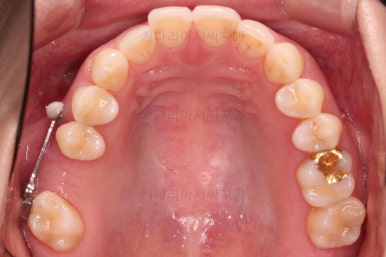

마찬가지로 부산치아교정비용 초진 시 입안의 모습입니다.

윗니 어금니가 하나 없는 상태였고요.

어금니가 없이 지낸지 꽤 시간이 흐른터라 뒤쪽 어금니가 앞으로 쓰러져 공간을 잠식하고 있었습니다.

물론 현재 모습대로 임플란트를 할려면 할 수 있지만 장기적으로 쓰러진 치아를 계속 사용하는게 치아수명에 바람직 하지 않죠.

임플란트도 원래 들어가야 할 어금니의 크기보다 많이 장가서 기능적으로 좋지 못하고요.

X-ray로 봤을 때 빈 공간에는 여러 가지 문제가 있었는데요.

뒷니가 쓰러졌다.

공간이 잠식 당했다.

어금니 위쪽 공기주머니가 잇몸뼈를 갉아먹으면서 잇몸뼈가 매우 얇아져있다.